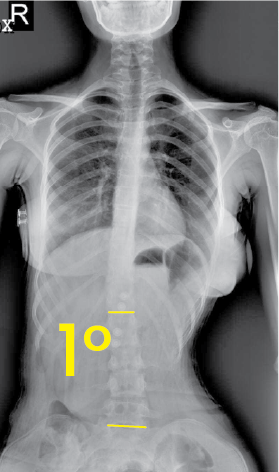

Göğüs bölgesinde 14 derece eğrilik gösteren omurga röntgeni görüntüsü.Göğüs ve karın bölgesini içeren, omurgada 1 derece eğrilik gösteren frontal X-ışını görüntüsü.